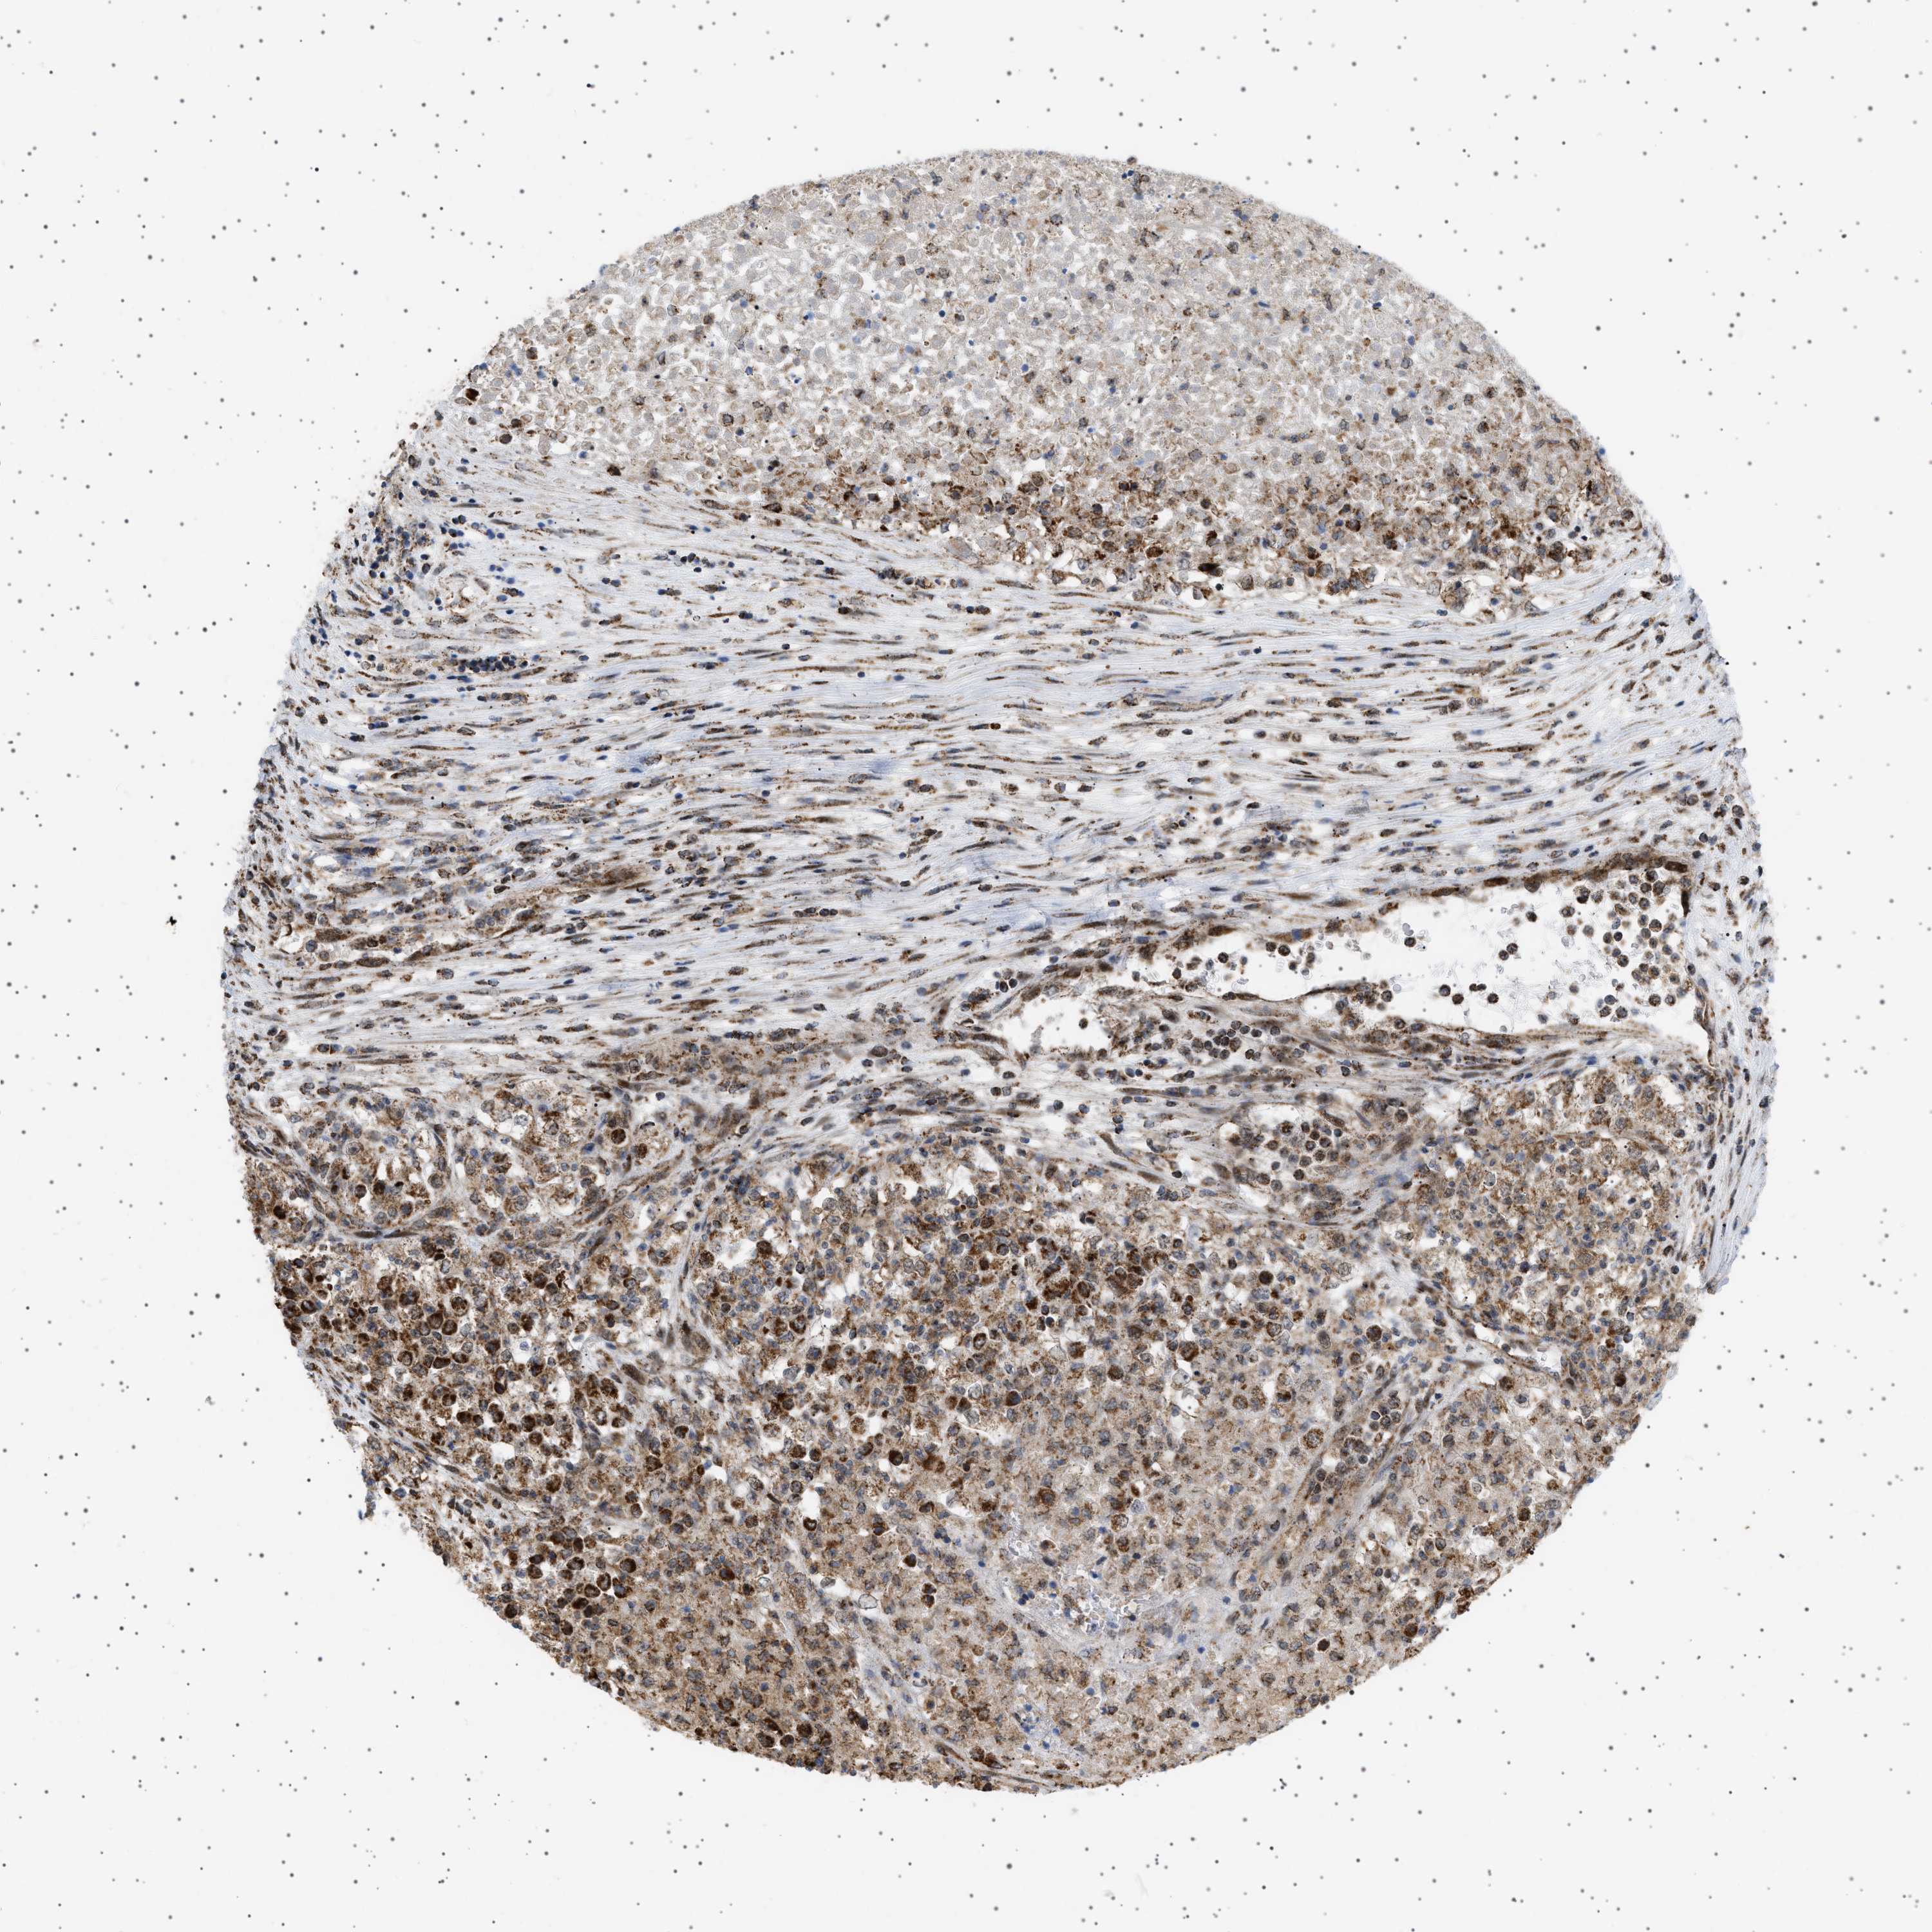

KIDNEY RENAL CLEAR CELL CARCINOMA (VALIDATION) - Interactive survival scatter ploti

The Survival Scatter plot shows the clinical status (i.e. dead or alive) for all individuals in the patient cohort, based on the same data that underlies the corresponding Kaplan-Meier plots. Patients that are alive at last time for follow-up are shown in blue and patients who have died during the study are shown in red.

The x-axis shows the expression levels (FPKM) of the investigated gene in the tumor tissue at the time of diagnosis. The y-axis shows the follow-up time after diagnosis (years). Both axes are complimented with kernel density curves demonstrating the data density over the axes. The top density plot shows the expression levels (FPKM) distribution among dead (red) and alive patients (blue). The right density plot shows the data density of the survived years of dead patients with high and low expression levels respectively, stratified using the cutoff indicated by the vertical dashed line through the Survival Scatter plot. This cutoff is automatically defined based on the FPKM cutoff that minimizes the p-score. The cutoff can be changed by dragging the vertical line or by entering a cutoff value in the square labeled "Current cut-off".

Under the Survival Scatter plot the p-score landscape (black curve; left axis) is shown together with dead median separation (red curve; right axis). Dead median separation is the difference in median mRNA expression between patients who have died with high and low expression, respectively. It is calculated as follows: median FPKM expression of dead patients with high expression - median FPKM expression of dead patients with low expression. This is intended to aid the user in visually exploring custom cutoffs and the associated p-scores and dead median separation.

Individual patient data is displayed and can be filtered by clicking on one or more of the category buttons on the top of the page. Categories describing expression level and patient information include: high, low, alive, dead, female, male and tumor stages. The scale of the x-axis can be toggled between linear and log-scale by clicking on the "x log" button. Mouse-over function shows TCGA ID, patient information and mRNA expression (FPKM) for each patient.

& Survival analysisi

Kaplan-Meier plots summarize results from analysis of correlation between mRNA expression level and patient survival. Patients were divided based on level of expression into one of the two groups "low" (under cut off) or "high" (over cut off). X-axis shows time for survival (years) and y-axis shows the probability of survival, where 1.0 corresponds to 100 percent.

MELK is validated prognostic, high expression is unfavorable in Kidney Renal Clear Cell Carcinoma (validation)

: 3.58

Average pTPM 3.3

Number of samples 100